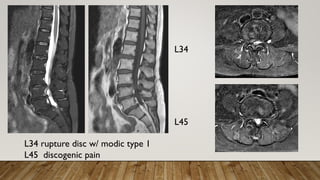

CASE 3

• Low back pain for 1 months

• VAS 10

• Radiation to right leg

• More painful when flexed

• Claudication +

• Medication at clinic and

rehab but in vain

L34

L45

L34 rupture disc w/ modic type 1

L45 discogenic pain

Left L34 discography with epidural spreading

Left L45 discography

PAIN SCORE

• Pre interventionVAS 10

• Back pain improved toVAS 1 after 1

week

• Right leg soreness at night